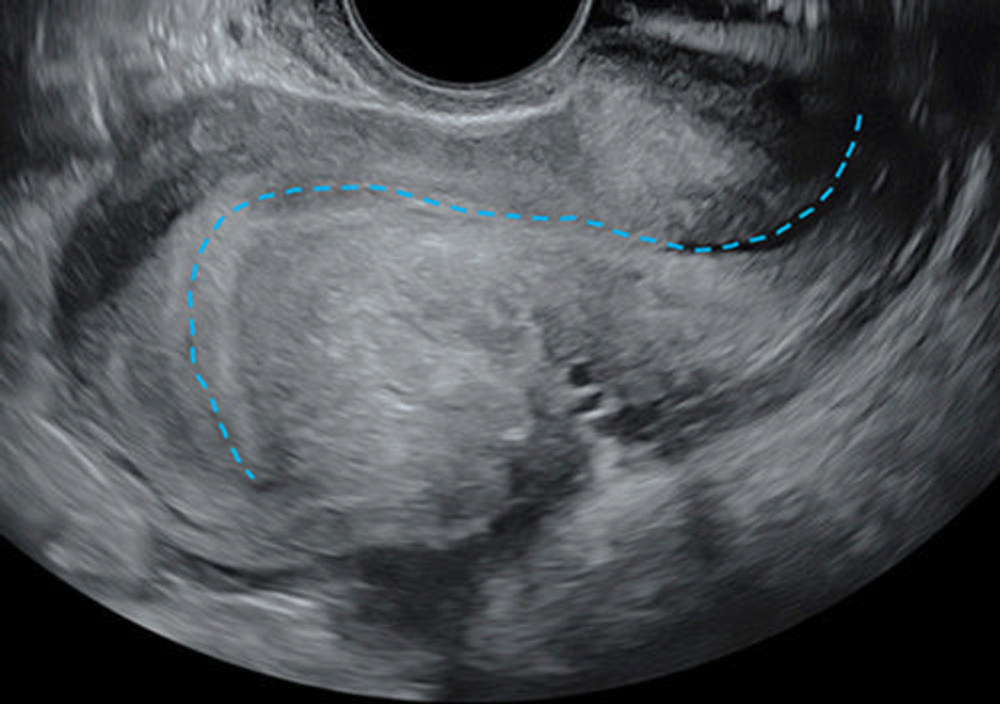

Figure 4. Transvaginal US in a 41-year-old patient with chronic pelvic pain and dyschezia shows the “question mark sign” uterine configuration. Longitudinal view shows an abnormal uterine configuration in which the uterus is sharply retroflexed because of deep endometriosis that is tethering the posterior cervix to the uterine corpus. This observation is usually identified by abnormal endometrial axis with sharp retroflection of the uterine fundus (dashed blue line) and constitutes a category B (ie, indirect endometriosis) observation.

High-res (TIF) version